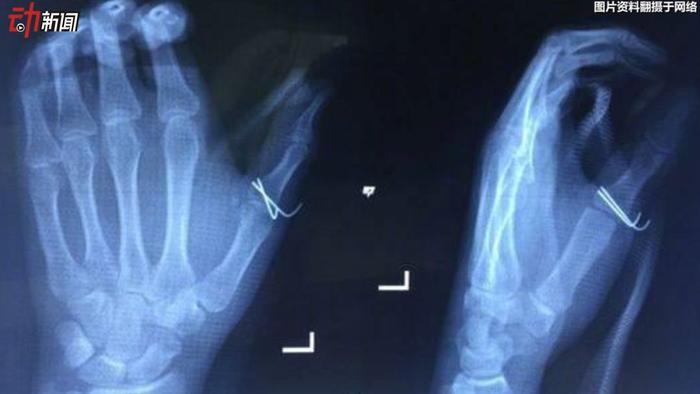

▲家人听到小袁的惨叫赶到,随即将他送往湖南省人民医院就诊。X光检查发现,其左手拇指近节指骨骨折。

▲医生为小袁做了2小时的手术,但由于伤口较深,创面较大,将来可能出现瘢痕挛缩,影响受伤手指的关节活动度。